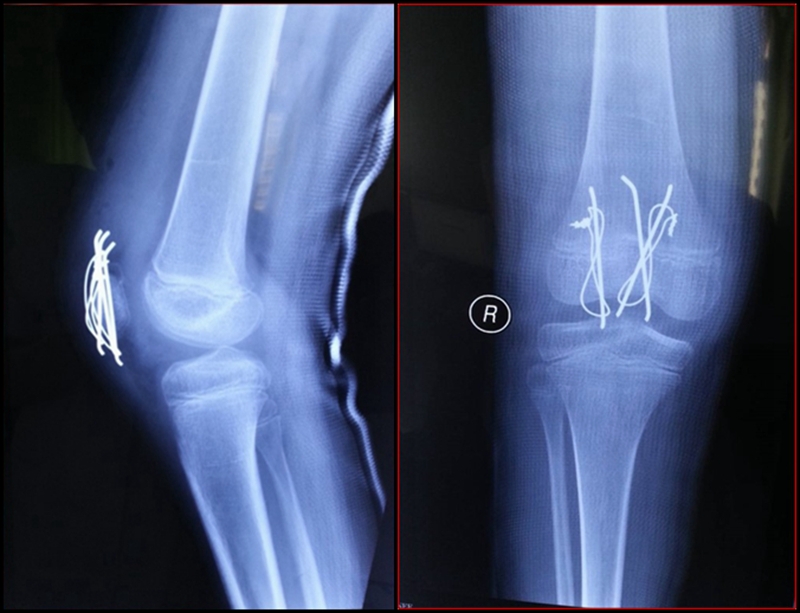

图2 受伤3周X线片

现病史:患儿于3周前下台阶时踩空而不慎摔伤右膝,当即感右膝肿胀、疼痛、不敢活动。于当地县医院就诊,行右膝拍片后诊为“右膝软组织损伤”,建议石膏固定3周。患儿于伤后3周门诊复查,再次拍片后诊为“右髌骨骨折”,建议手术治疗,家属为进一步诊治来我院门诊,门诊以“右髌骨套状撕脱骨折”收入院。

考虑此患儿伤后已3周,组织全科讨论,确定诊断为:髌骨上极陈旧性套状撕脱骨折。充分与家属沟通远期预后。